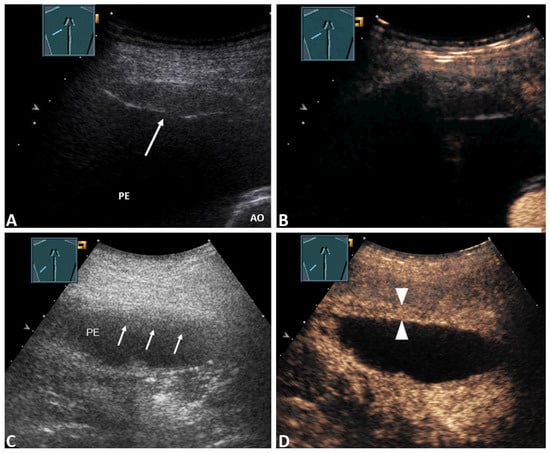

| Pleural thickening with marked enhancement (Figure 2B and Figure 3D) | 27 (32.5%) | 20 (47.6%) | 7 (17.1%) | 0.005 * |

| Pleural thickening with absent or reduced enhancement or no pleural thickening (Figure 3B) | 56 (67.5%) | 22 (52.4%) | 34 (82.9%) | |

| Inhomogeneous enhancement of lung consolidation (Figure 5B–D) | 25 (30.1%) | 19 (45.2%) | 6 (14.6%) | 0.004 * |